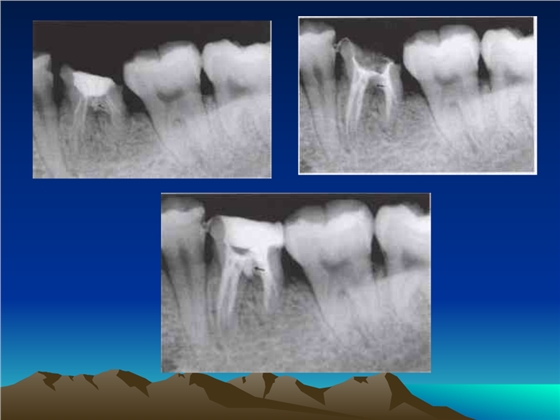

首頁牙體牙髓 鈣化細(xì)小根管的處理技巧

鈣化細(xì)小根管的處理技巧